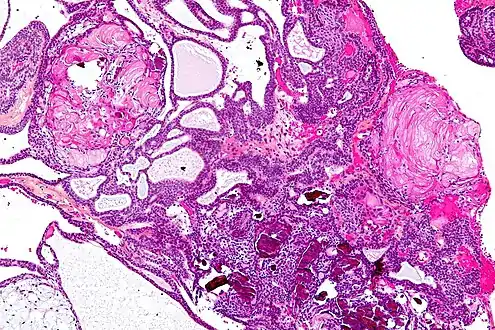

| Very low magnification micrograph of an adamantinomatous craniopharyngioma. HPS stain. | |

On macroscopic examination, craniopharyngiomas are cystic or partially cystic with solid areas. On light microscopy, the cysts are seen to be lined by stratified squamous epithelium. Keratin pearls may also be seen. The cysts are usually filled with a yellow, viscous fluid rich in cholesterol crystals. Of a long list of possible symptoms, the most common presentations include headaches, growth failure, and bitemporal hemianopsia.

Micrograph showing the characteristic features of an adamantinomatous craniopharyngioma - cystic spaces, calcifications, and "wet" keratin, HPS stain